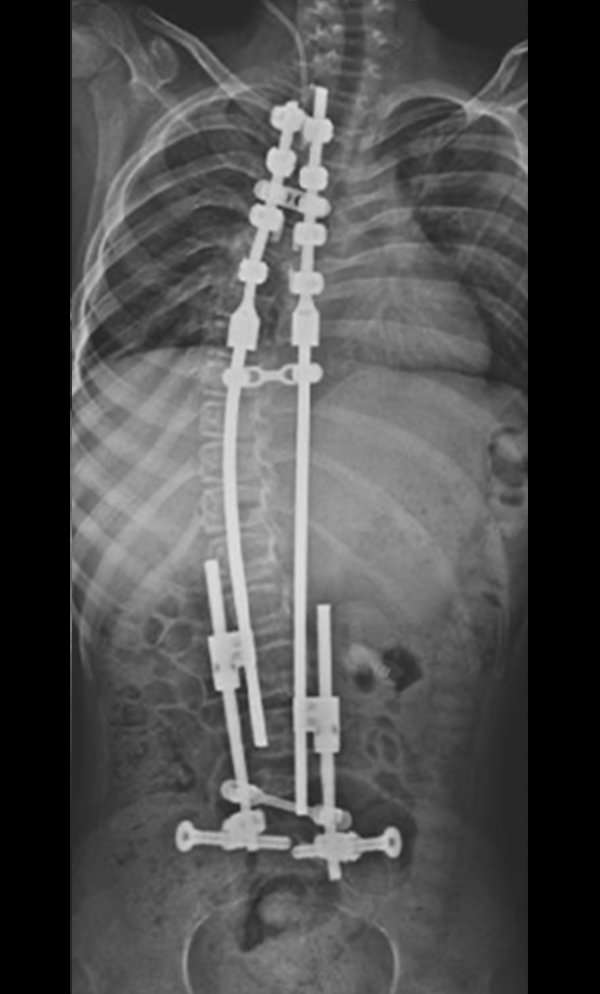

Gallery : Before - After